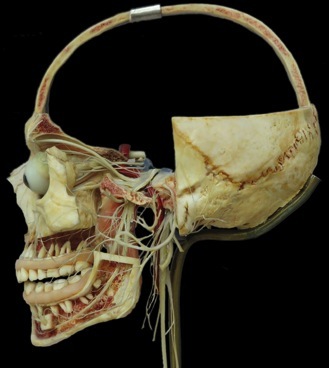

Le système nerveux central. Il est constitué de l'encéphale (cerveau et cervelet protégés par la boîte crânienne) et de la moelle épinière qui est logée dans la colonne vertébrale.

Le système nerveux périphérique (en noir) qui est formé des nerfs et ganglions).

Chaque neurone possède des milliers de dendrites qui le relient à ses voisins. Ci-contre les neurones du cortex cérébral. La matière grise est constituée des amas de corps cellulaires de neurones tandis que la matière blanche est formée des axones.

Le système nerveux n'est pas constitué de neurones uniquement. Des cellules gliales (10 fois plus nombreuses) ont la fonction d'alimenter les neurones.

Les neurones sont regroupés en faisceaux et protégés par différentes enveloppes de tissu conjonctif (protection et isolation): ce sont les nerfs.